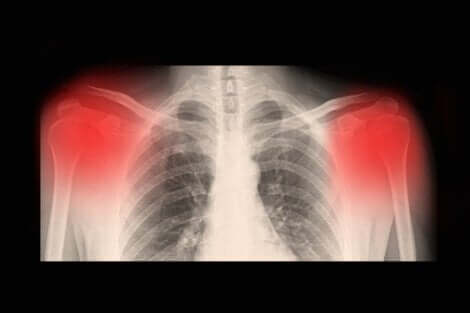

Generalmente la diagnosi viene effettuata in seguito a una visita medica, accompagnata di solito da raggi X, tomografia assiale computerizzata (TAC) o risonanza magnetica. Un’ecografia ad alta risoluzione può essere indicata per valutare il grado di evoluzione dell’artrosi.